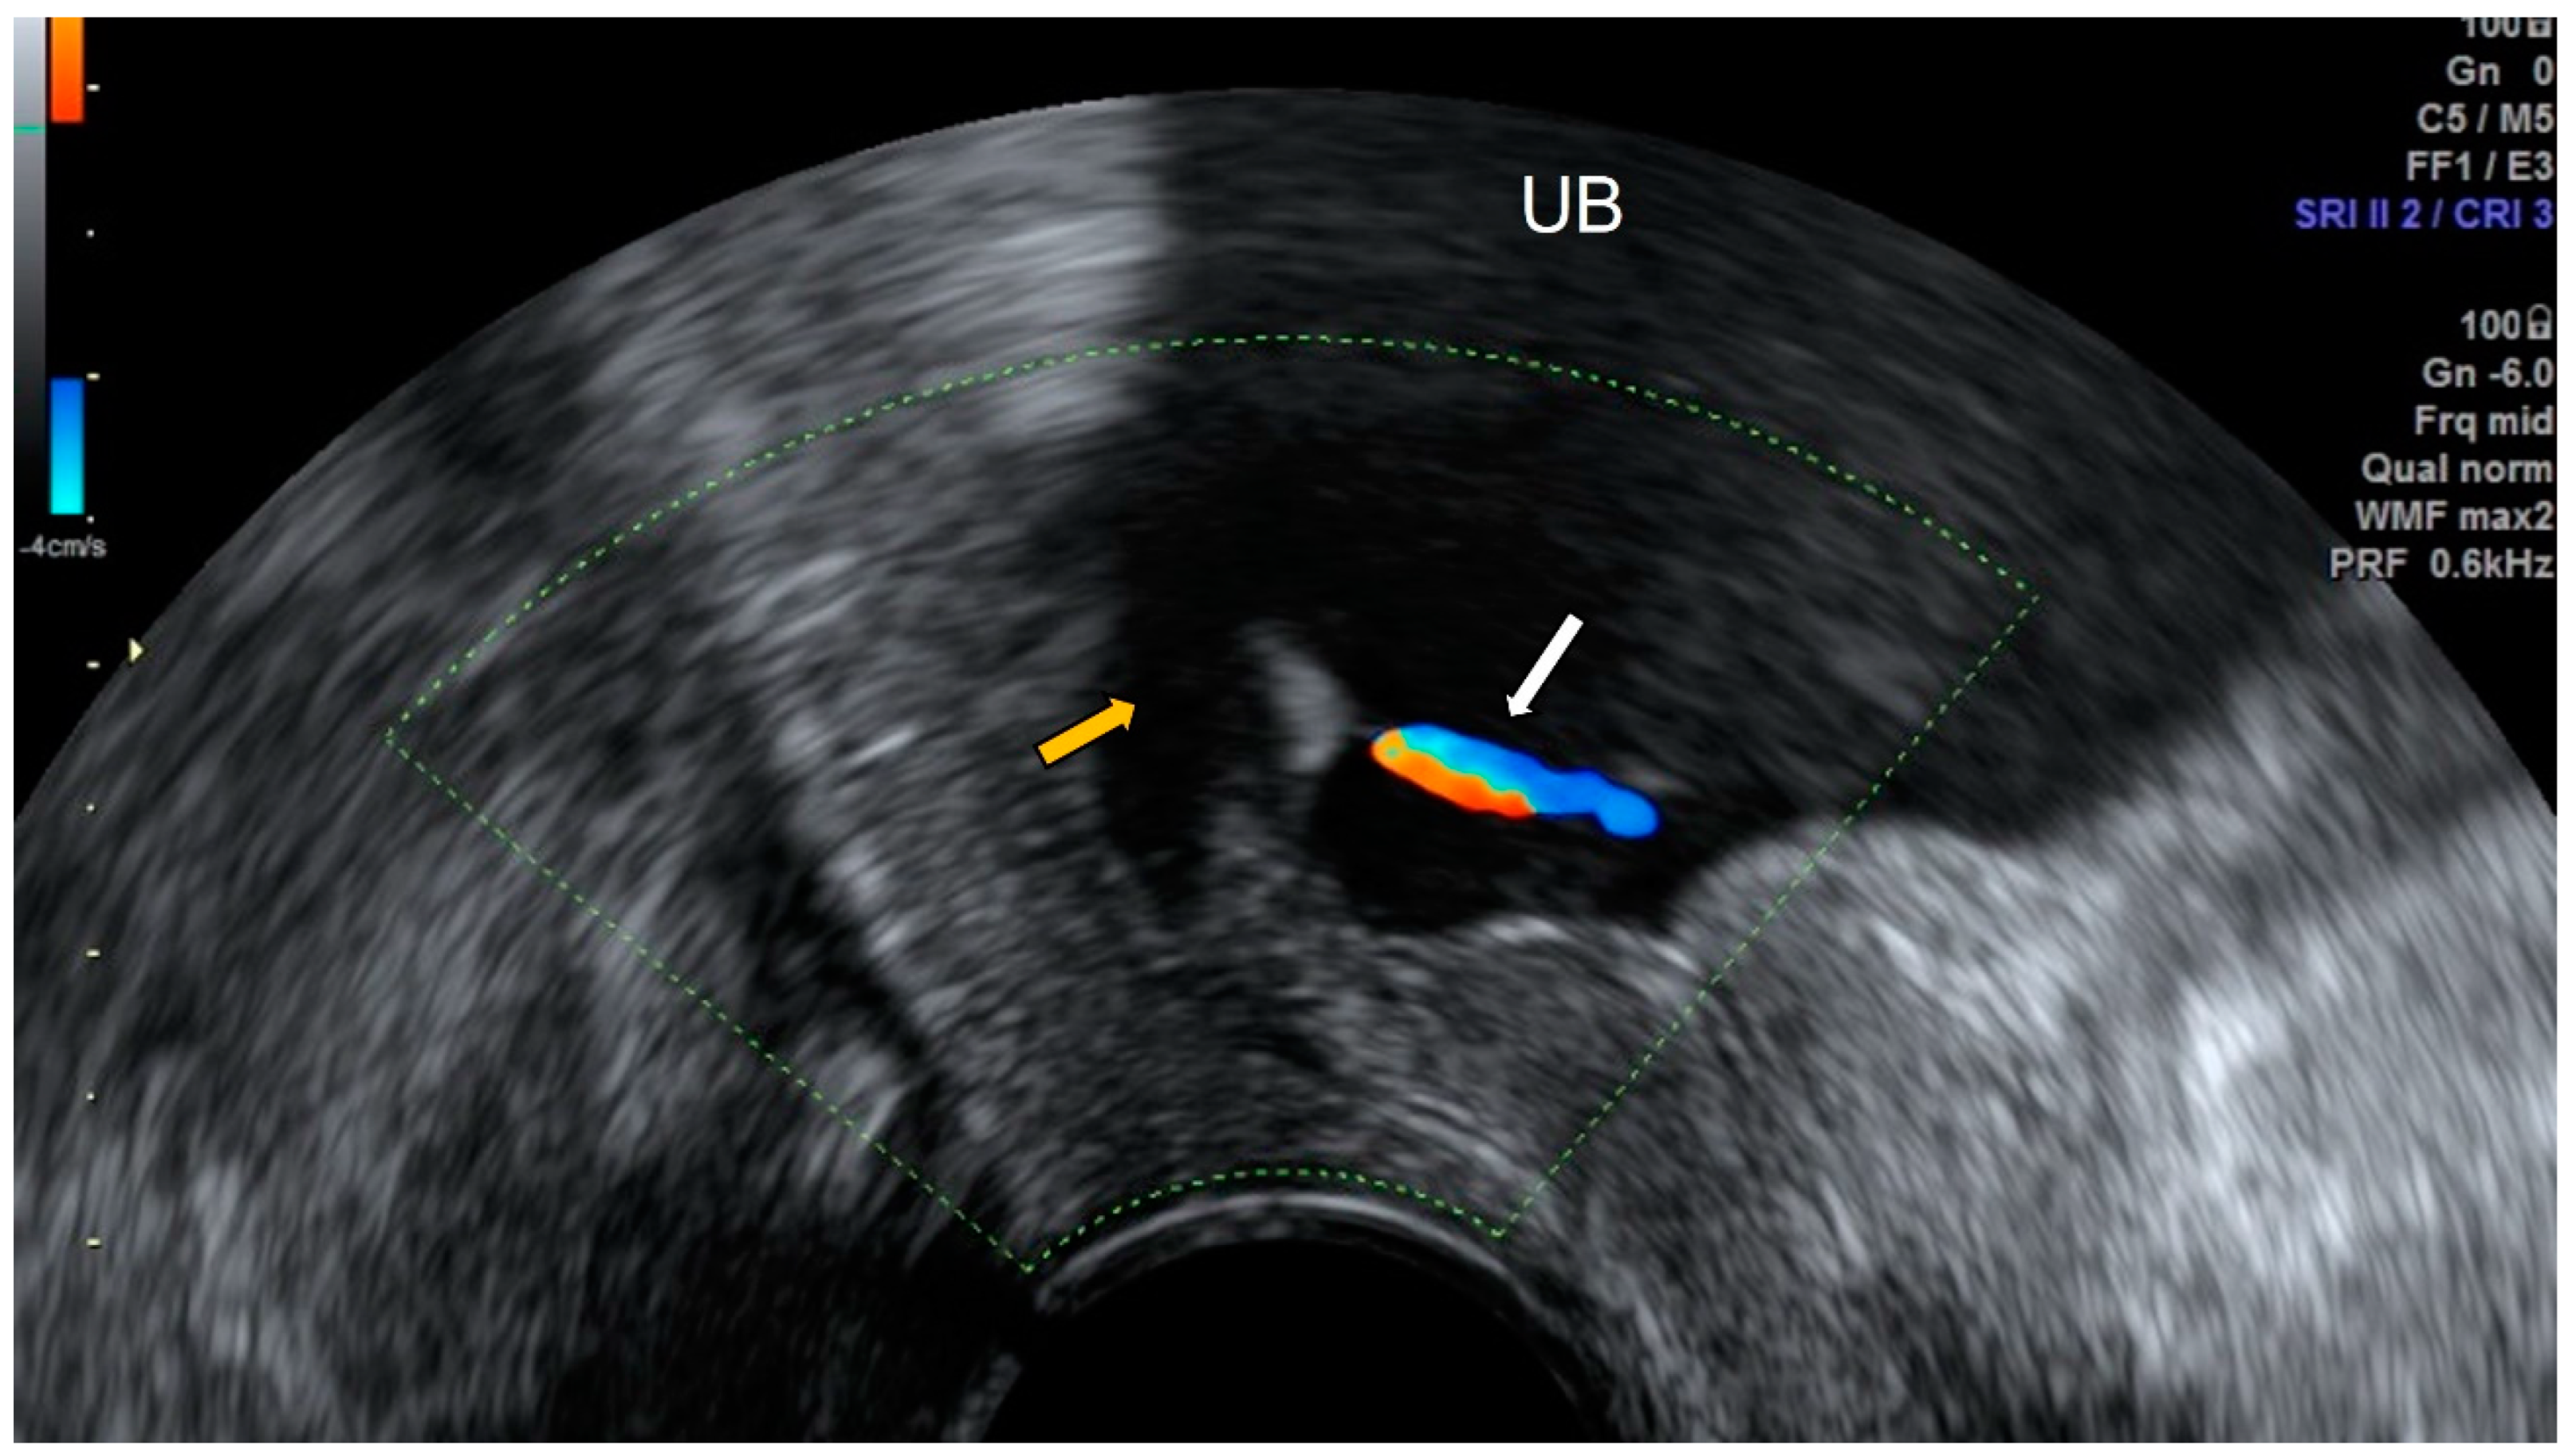

3.1. Mega Ureter and Ureterocele

3.2. Benign and Malignant Bladder Pathology